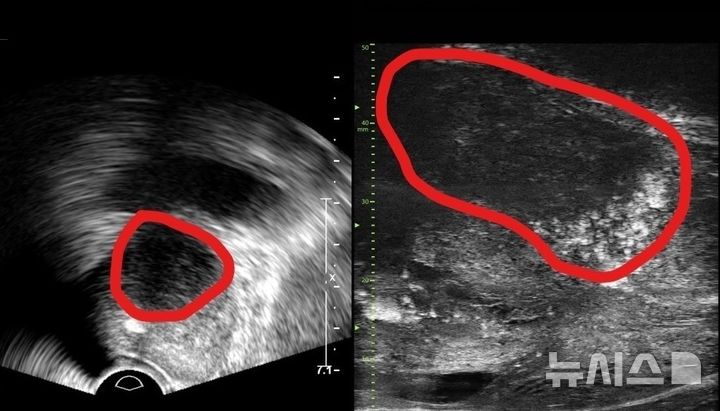

[서울=뉴시스] 기존 전립선 초음파 사진(좌) 및 최신 초음파 사진. 기존 초음파는 전립선 부위(동그라미 친 부분)의 음영 차이로만 병변을 확인했지만, 마이크로 초음파는 높은 해상도를 통해 종양과 주변 조직의 모양까지 확인할 수 있다. (사진= 분당서울대병원 제공)

[서울=뉴시스] 류난영 기자 = 분당서울대병원 비뇨의학과는 기존 초음파보다 3배 더 높은 해상도의 실시간 영상을 통해 전립선 종양 평가가 가능한 마이크로 초음파 장비를 국내 최초로 도입했다고 24일 밝혔다.

29MHz 마이크로 초음파를 사용하는 이 장비는 전립선과 주변의 해부학적 구조를 선명히 표시하고 표적 조직검사를 유도한다. 의심 영역을 실시간으로 확인하면서 전립선 조직의 미세한 변화와 병변을 식별하고 조직검사 채취를 위한 바늘을 정확한 위치에 삽입할 수 있다는 장점이 있다.

기존의 경직장 초음파는 해상도가 낮아 전립선 종양, 특히 작은 암 병변을 감지하는 데 한계가 있었다. 하지만 마이크로 초음파의 높은 해상도와 실시간 영상의 시각화는 자기공명영상(MRI)으로 발견할 수 없는 전립선암을 찾을 때도 충분히 기여할 것으로 기대하고 있다. MRI 검사 보다 환자의 신체적, 심리적, 경제적 부담도 적을 수밖에 없다.